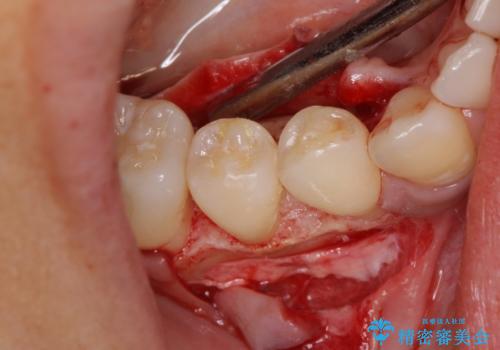

患者様は、他院で右下の歯を抜歯かもと言われました。全体の歯周病はなく、右下の1歯だけ骨が極端に減少していました(初診時歯周ポケット7mm。通常は3mm以下。)。その歯だけ咬合が強いことが原因と考えられたため、咬合を弱くする処置と減少した骨を再生する処置が必要になりました。

骨の再生治療手術をして10か月経過観察をしたのち、骨を平坦化する手術を行い、治療終了となりました。